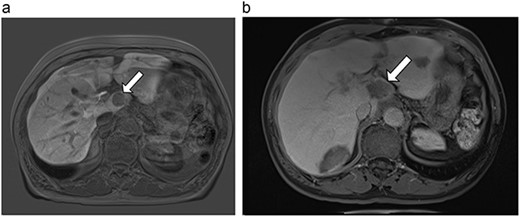

(a) Pre-ablation MRI demonstrating 14 mm lesion in caudate lobe of liver. (b) Post-ablation MRI (23 days postoperatively) demonstrating 23.8 mm complete ablation of caudate lesion.

| 4 (6a,b) | 51, M | Colon adenocarcinoma | 6 cycles FOLFOX | 4 | Laparoscopic microwave ablation | 14 | 23.8 | 9.8 | 13 | Yes |

Postoperative MRIs were obtained at a median of 19 days postoperatively (14–23 days). Median ablation margin (difference between ablation zone and original tumor size) was 22.95 mm (9.3–34.4 mm). At a median follow-up of 10.5 months (6–15 months), one of six (17%) caudate ablations had evidence of local recurrence. At diagnosis, this tumor had been abutting 180 degrees of the vena cava, and its proximity to the posterior hilum made a more aggressive burn inadvisable. Time to recurrence for this patient was 6 months. There were no recurrences in non-caudate ablations in this same patient. No long-term complications were observed in any patients.